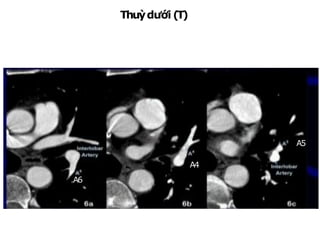

• 84.

TA: thân trước(truncus anterior) IA: ĐM gian thùy BT: thân đáy (basal trunk) A1: đỉnh A2: sau A3: trước A4: ngoài A5: trong A6: trên A7: đáy trong A8: đáy trước A9: đáy ngoài A10: đáy sau ĐỘNG MẠCH PHỔI (P)

Thuỳ dưới (P): - ‐Nh á n hA6:từĐMC gian thuỳ ngang mức mặt sau trong - ‐ N h á n hA7:đáyt r o n g - ‐ c ạ n htim, từ thân đáyđi xuốngvàotrong A 9 - ‐ 10 A7 A8 A10 A9 A8 A7

IA: ĐM gianthùy BT: thân đáy (basal trunk) A1 + A2: đỉnh sau A3: trước A4: ngoài A5: trong A6: trên A7 + A8: đáy trước trong A9: đáy ngoài A10: đáy sau ĐỘNG MẠCH PHỔI (T)

• 89.

Thuỳtrên(T) NhánhA1+2:từ mặttrênĐMphổi (T)đilêntrên NhánhA3:đi ratrước A3 A1+ 2 A1+ 2 A3 A1+ 2

• 90.

Thuỳtrên(T) NhánhA4:lưỡi trên, từmặttrước ĐM gianthuỳđi lên trên A4 A5 A6

• 91.

Thuỳdưới (T) NhánhA6:từ ĐMgianthuỳngangmứchoặcngaytrênchỗ xuất phátĐMthuỳlưỡi, đi rasau A4 A5 A6

• 92.

Thuỳdưới(T): NhánhA7+8:từ thân đáy đixuống,ra trước, vào trong NhánhA9:rangoài NhánhA10:rasau A9 A10 A8 A7